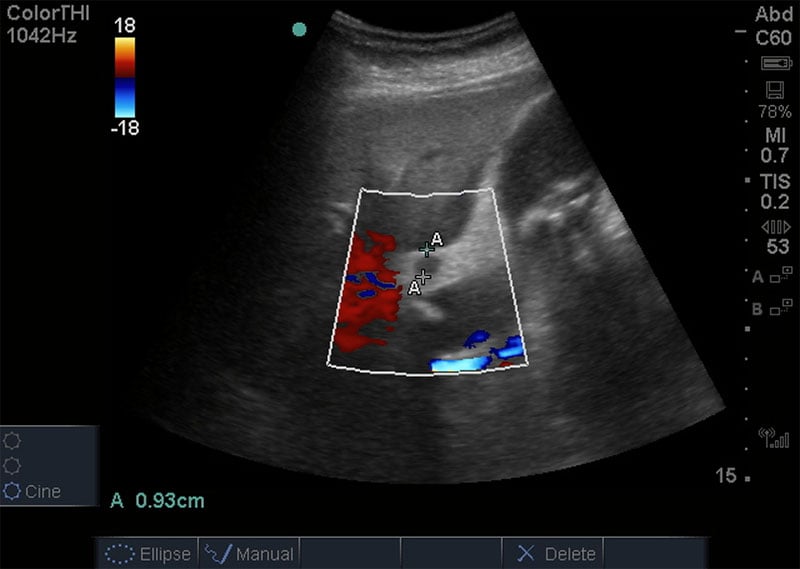

40 y/o female with history of hyperlipidemia, obesity, and GERD presenting with upper abdominal pain. The goals of this case are to evaluate initial evaluation of young female with upper abdominal pain and review ultrasound findings of acute.